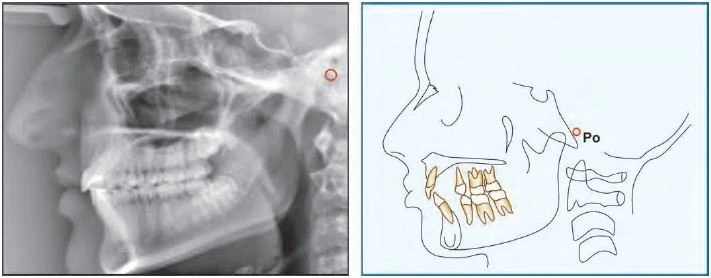

Porion (Po) Đỉnh của ống tai ngoài. Đôi khi do khó xác định porion nên sử dụng đỉnh của bóng thanh tai, điểm này được gọi là “machine porion”